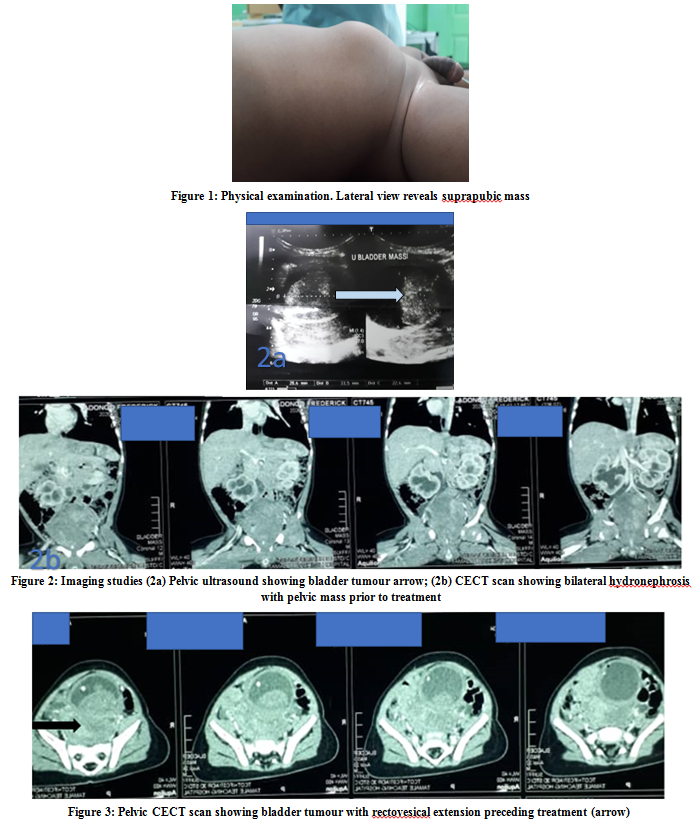

Infant Bladder Rhabdomyosarcoma in a Shared-Care Centre in Ghana: Case Report and Review of the Literature

Edwin M.T. Yenli, Kingsley A Bimpong, Nihad Salifu, Peter G. Kwarteng, Ernest K. Cheyuo, Yaninga H. Fuseini, Dieu-Donnee Anyekase, Emmanuel Akorli, Edmund Der

International Journal of Innovative Research in Medical Science·May 26, 2021